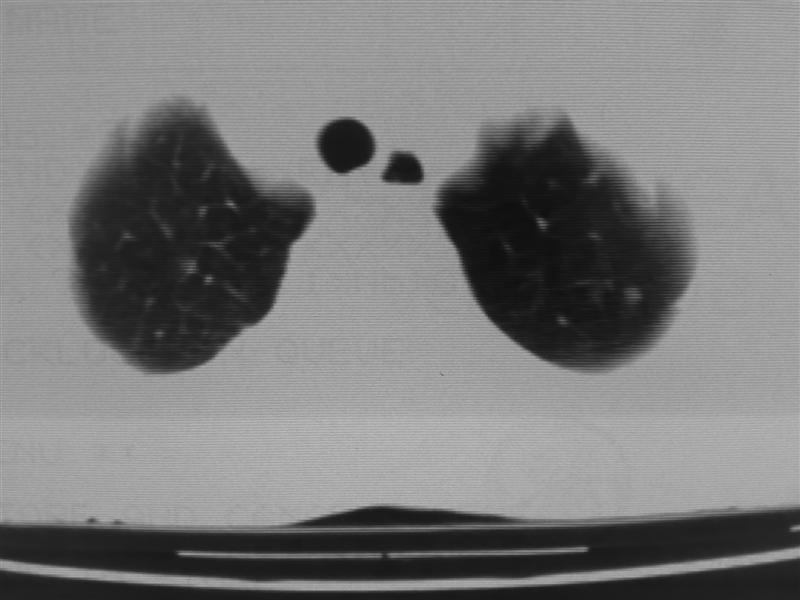

标题: CT10080:F76Y,各位老师发表高见!!! [打印本页]

标题: CT10080:F76Y,各位老师发表高见!!!

右下肺周围型肺癌伴双肺右侧叶间 胸膜及右肺门淋巴结转移

考虑:肺癌伴肺、胸膜 纵隔淋巴结转移可能性大!